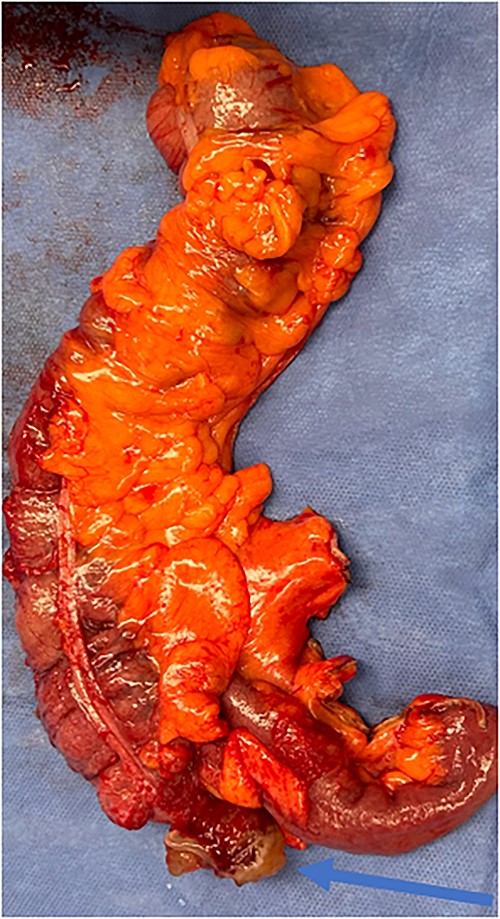

An exploratory laparotomy with a midline incision was performed. Upon inspection of the abdominal cavity, there was no evidence of metastatic disease to the peritoneum, omentum, or liver. A perforated mucinous mass with mucinous collection was identified in the right lower quadrant by the appendix with an additional mucinous collection in the pelvis. Given the appendiceal and cecal involvement, the decision was made to perform a right hemicolectomy and primary anastomosis. Given that this was favored to be a malignant process intraoperatively, the decision was made to perform a right hemicolectomy over a limited ileocolic resection. Lymph nodes were also included due to the extent of the surgical resection. The specimens were sent to pathology. The abdomen was further inspected and subsequently closed (Figs 3–5). The patient tolerated the procedure well, was extubated in the operating room, and recovered in the post-anesthesia care unit in stable condition. The patient was observed postoperatively and was discharged home on postoperative Day 8. The duration of follow-up is 4 months without clinical concerns during follow-up. The final pathology of the specimens revealed LAMN with perforation and associated calcifications. The proximal and distal resection margins were free of neoplasia, and 42 lymph nodes were negative for tumor. There was presence of acellular mucin in the tissue sample, suggesting a favorable prognosis according to previous studies demonstrating that 96% of patients with acellular extra-appendiceal mucin were disease-free at 52 months [5]. Follow-up via surveillance magnetic resonance imaging (MRI) every 6 months, and colonoscopy were recommended. The patient was referred for blood testing, including the tumor marker carcinoembryonic antigen (CEA), which has been unremarkable.

Specimen including terminal ileum, ascending colon containing the perforated mucinous mass at the base of the cecum (blue arrow).